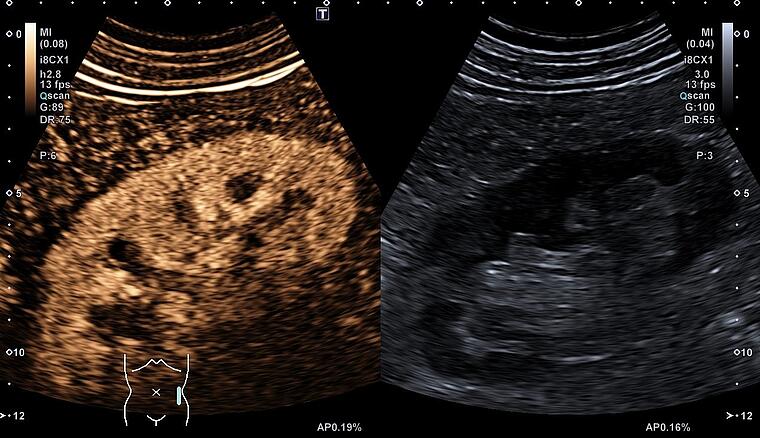

Die Sonografie als das am häufigsten eingesetzte bildgebende Verfahren ist als „Fortsetzung der klinischen Untersuchung mit technischen Mitteln“ aus dem ärztlichen Alltag nicht mehr wegzudenken. Mit dem Ausbau des zentralen Ultraschalllabors am St. Josefkrankenhaus wollen wir das gesamte Spektrum der Methode unseren Patienten zugutekommen lassen. Im Rahmen des ersten „Ultraschallnachmittags am St. Josefskrankenhaus“ möchten wir Ihnen in diesem Jahr aus der Vielfalt der sonografischen Möglichkeiten, Grundlagen und praktische Aspekte der kontrastverstärkten Sonografie sowohl im Bereich der Abdomensonographie, als auch der Thoraxsonografie vorstellen.

17.45 Uhr Leberherddiagnostik mit Ultraschall

Prof. Dr. A. Schuler